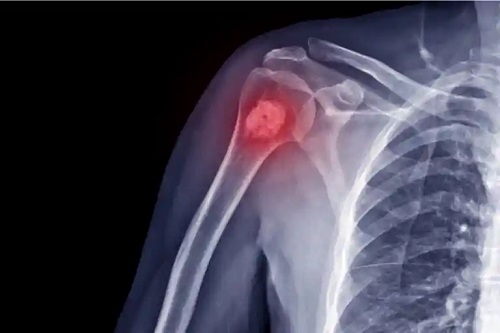

Acest cancer debutează la capetele oaselor brațelor sau picioarelor, dar apare și în alte oase. Cel mai frecvent apare în următoarele zone:

- Sub umăr sau la nivelul humerusului proximal

De obicei, diagnosticul se stabilește pe baza interviului clinic și a istoricului de sănătate, alături de anumite teste. De obicei, începe cu efectuarea de radiografii, care sunt completate de un RMN. Odată ce problema este detectată și zona este identificată, are loc o biopsie.